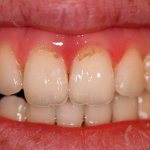

В детства родители постоянно твердили нам о том, что зубы необходимо чистить тщательно, утром и вечером. То ли из-за возраста или в связи с недостатком времени, многие из нас забыли об этом важном правиле и как оказалось очень зря. Одна из основных причин возникновения кровоточивости десен и как следствие их воспаления, это – неправильная и не постоянная гигиена полости рта. Доказано, что после чистки зубов, уже через 4-5 часов, на поверхности эмали вновь скапливаются вредоносные микроорганизмы, которые постепенно преобразуются в мягкий налет, а затем и в твердый камень. Особенно их распространению содействуют углеводы, поглощая их, бактерии выделяют особые кислоты, которые негативно влияют на здоровье зубов. Из-за налета, десна становятся слабыми и воспаленными, а увеличение зубных отложений приводит к образованию десневых карманов. Сначала у пациента возникает заболевание гингивит, а если воспалительный процесс своевременно не остановить и вылечить, появляется его осложнение пародонтит.

Существует несколько причин кровоточивости и заболевания десен:

Травмирование мягких тканей.

Поранить десну достаточно легко, это может случиться во время приема пищи, и из-за неправильно установленных протезов. В образовавшуюся рану попадают бактерии, которые могут вызвать воспаление.